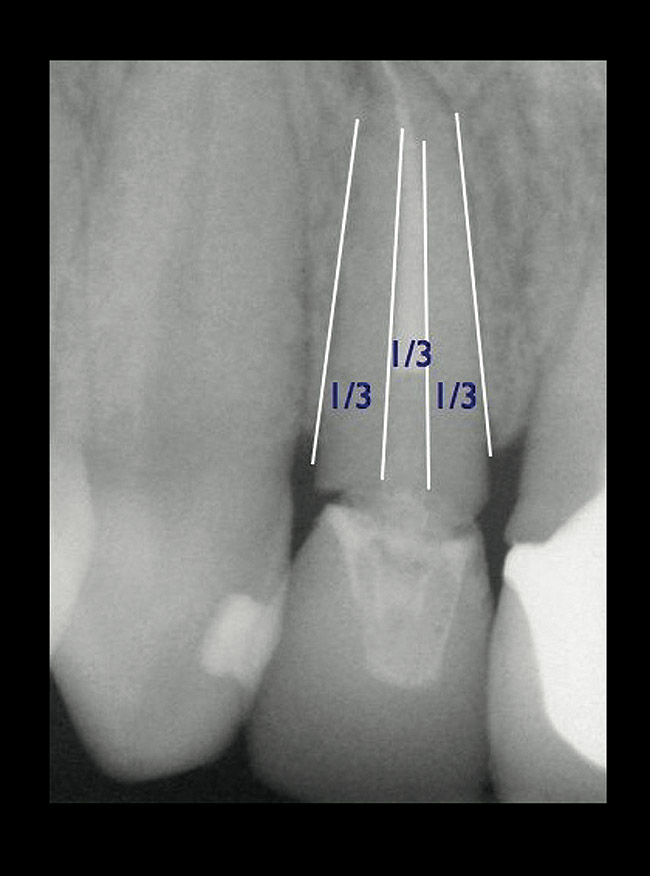

If the tooth has been endodontically treated, the remaining tooth structure relative to the post space needs to be evaluated. The Rule of Thirds is used in this situation. It states that the canal or canal space preparation should not be any wider than one third the mesiodistal root diameter after the endodontic access (Figure 3).3 Once the clinician determines whether adequate tooth structure is present, the second area to evaluate is the distance of the fracture/caries from the crest of bone. To avoid biological width impingement, the minimum distance needed from the osseous crest to the final margin placement is 2.5 mm (Figure 4). As determined in cadaver studies, this consists of approximately 1 mm of connective tissue attachment, 1 mm of junctional epithelium, and 0.5 mm of gingival sulcus.4 This measurement is meant as a guideline and not an absolute number, as it has been shown to have individual variability.5 This actual dimension for the individual patient can be predictably determined by sounding to bone on the adjacent teeth to more closely determine the individual’s biologic width.6

Figure 3  EVALUATION PARAMETERS  The Rule of Thirds: The canal or canal space preparation should not be any wider than one third the mesiodistal root diameter after the endodontic access.

Figure 3